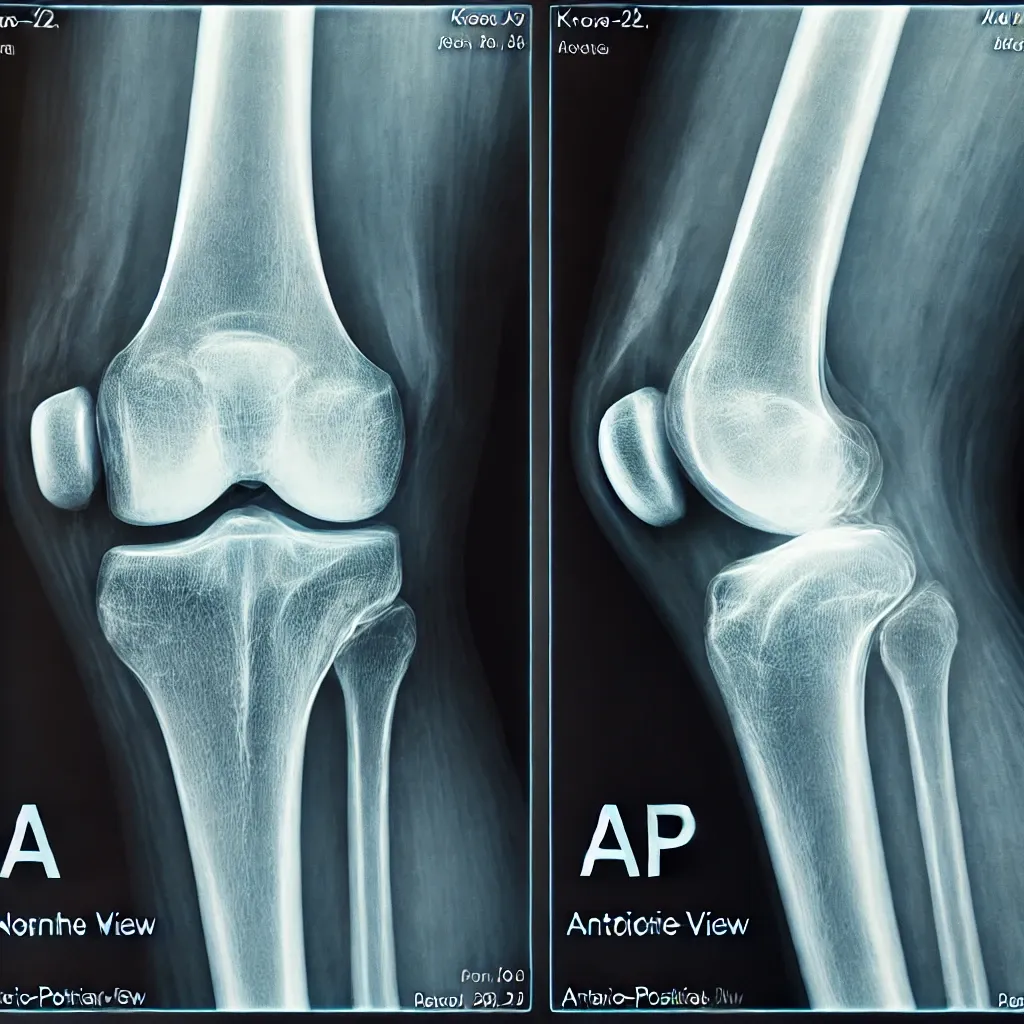

Can you guess which knee is affected by arthritis?

-The answer is the second picture.